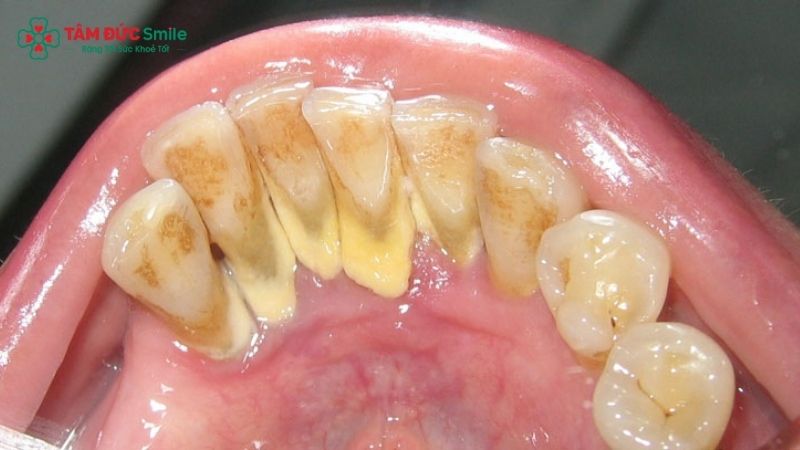

The formation of cavities begins with plaque, a sticky film of bacteria that constantly forms on the teeth. When you consume foods and drinks high in sugar and cavities-causing carbohydrates, bacteria in plaque feed on these sugars and produce acids. These acids repeatedly attack the enamel, causing mineral loss and weakening the tooth surface.

Poor oral hygiene, such as infrequent brushing and flossing, allows plaque to remain on the teeth longer, increasing the risk of tooth decay.

- Visible pits, holes, or dark spots on the teeth